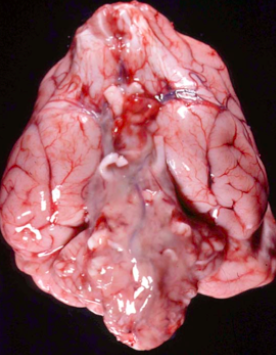

grossly, what is the main feature of bacterial meningitis?

cloudiness on the ventral aspect of the brain, unable to see the blood vessels as clearly

Q

this came from a young calf, 2 days old. what is this probbaly?

A

bacterial meningitis